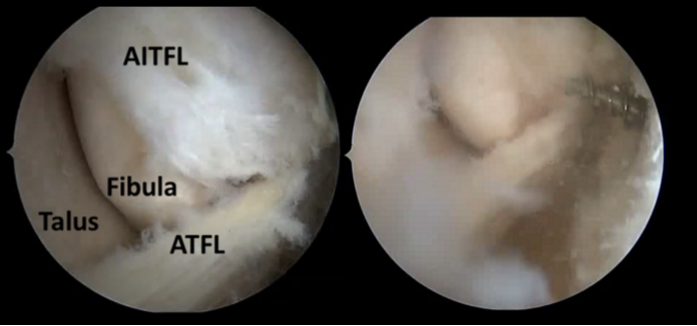

| 圖二、內視鏡下的外側韌帶修補,圖左為內視鏡中看到的外側韌帶,圖右顯示將帶線錨釘置入韌帶的附著點。 |